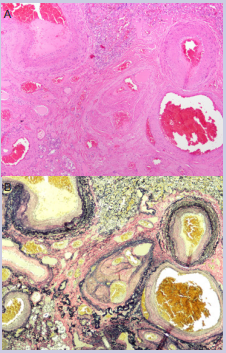

EVG elastic stains in three blocks that contained the vascular malformation confirmed the presence of mostly veins with a few arteries in the malformation [Figure 7].

Figure 7: A) Higher power view of the abnormal vascular malformation containing various blood vessels (40x). Rare small veins (center) contained multiple vascular lumens and other features suggestive of recurrent thrombosis and recanalization. B) Elastic Van Gieson (EVG) stain (40x).

Classic features of an arterio-venous malformation, a capillary free communication between the pulmonary arterial and pulmonary venous circulations, were absent.